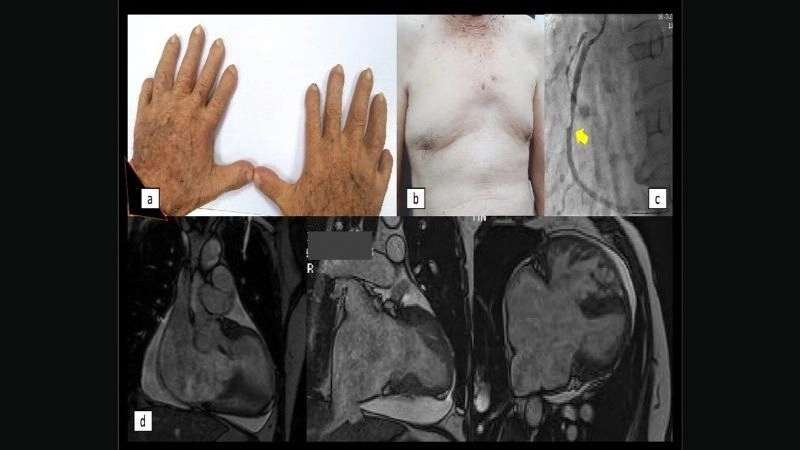

Images visual examples of Holt-Oram Syndrome

Visual examples show children and adults with upper limb differences like missing thumbs, underdeveloped forearms, and associated heart defects, helping identify typical manifestations of Holt-Oram Syndrome for educational purposes.